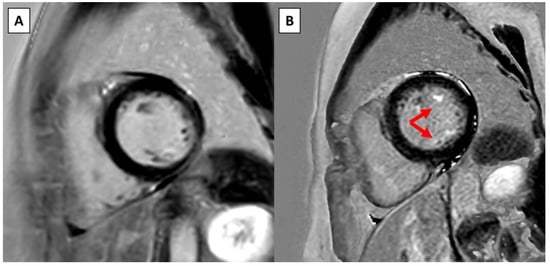

At follow-up CMR, six out of eight (75.0%) 24 h Holter recordings were performed prior to the follow-up CMR resulting in a median time of 2.2 months before CMR. In three (37.5%) cases the Holter triggered the repeat CMR, while in the remaining cases the Holter was obtained in the routine follow-up. Upon follow-up CMR, four (50.0%) patients had a new LGE present. New myocardial LGE was present in the basal inferolateral segment of one patient. New papillary muscle LGE was present in three patients, and all of them had new LGE in both papillary muscles (Figure 1) and one of these had new LGE in both the basal and mid inferolateral segments and both papillary muscles (Supplementary Figure S2). The change in LGE from baseline is presented in Supplementary Figure S3.

Figure 1. Example of new LGE on serial CMR in a patient without surgical intervention. (A) Short-axis view on the baseline CMR at the level of the papillary muscles. (B) Short-axis view at the same level approximately 4 years later shows new LGE in both papillary muscles (red arrows).

From a clinical perspective, one patient remained free from arrhythmias and one patient underwent catheter ablation for symptomatic PVC ectopy from the posterior papillary muscle despite treatment with beta-blockers and flecainide. The catheter ablation reduced the PVC burden from 5% to 2%. Four patients (50.0%) presented with either increased arrhythmia burden, presyncope or syncope. In one patient without any LGE who presented with syncope, the PVS was negative. One patient with baseline LGE in the posterior papillary muscle and new LGE in the basal inferolateral segment presented with an increase in PVC and nsVT burden and also had a negative PVS. In both these patients, the ventricular arrhythmias were appropriately suppressed with beta-blockers. Two patients had positive PVS and received an ICD. The first patient presented with nsVT and presyncope during exercise testing and had a new LGE in both papillary muscles. The second patient presented with presyncope and had a new LGE in both the basal and mid inferolateral segments and in both papillary muscles. None of them have received any ICD therapy under treatment with either betablockers or betablockers and flecainide, respectively. Upon repeat CMR, one patient showed disappearance of mitral valve regurgitation. At baseline, this patient had a mildly reduced LVEF with grade 1 mitral regurgitation, no LGE, and fulfilled the AMVP criteria before baseline CMR based on documented nsVT on Holter. Upon repeat CMR she was treated with betablockers and low dose ACE-inhibitors, and no mitral valve regurgitation was noted. The LVEF evolved from 48% to 53% upon repeat CMR.